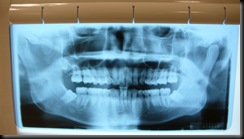

另一個消息是,我找了一個根管治療的醫師,我都說沒蛀牙不做根管,還是幫我照了牙齒的X光(一定是健保的怪規定),才發現我的智齒還沒長出來.牙醫一看到片子就說"要拔",什麼?我這輩子沒蛀過牙,為什麼也要受這種痛呢?我會怕呀!我查了一下Google,發現先進國家的人都會做這種預防性的治療.是沒有絕對要拔,但是因為不易清理,有可能會蛀掉,年紀愈大拔愈危險,所以我想拔.

P2220524我的牙